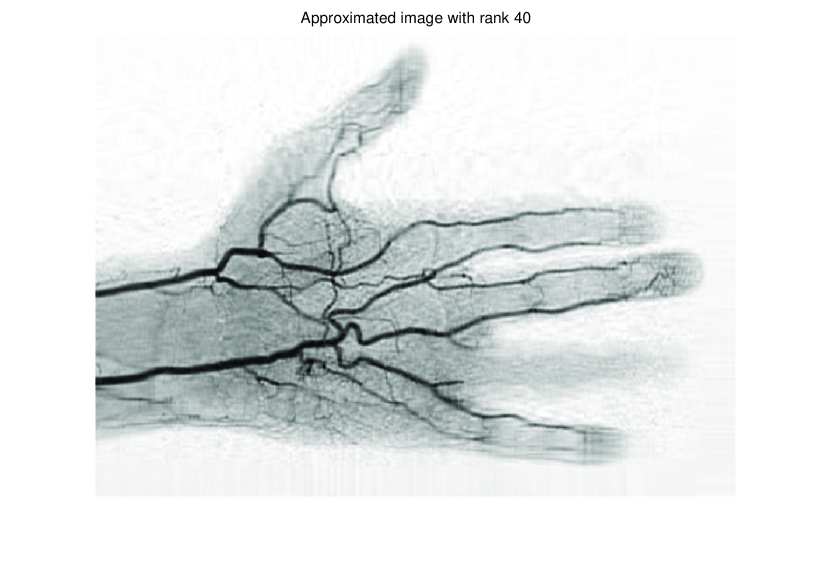

In this subsection, we demonstrate performances of ISVTA on image inpainting problems. The ISVTA is tested on some medical grace images (255×192255192255\times 192 Brain angiography image (BAI), 395×549395549395\times 549 Hand angiography image (HAI) and 419×400419400419\times 400 Intracranial venous image (IVI)). We use the SVD to obtain their approximated low-rank images with rank r=30,40,30𝑟304030r=30,40,30, respectively. Numerical results of ISVTA for theses low-rank image inpainting problems are reported in Table 5, 6, 7, 8.

Figure 4: Original 395×549395549395\times 549 HAI and its approximation with rank 40.

Refer to caption

Figure 5: Original 419×400419400419\times 400 IVI and its approximation with rank 30.

Table 5, 6 show that ISVTA performs powerful in finding a low-rank matrix on image inpainting problems. Indeed, we could get an exact low-rank image by the ISVTA by choosing proper a𝑎a. Moreover, it is necessary to point out that our method does not work well for all a>0𝑎0a>0, and we can find that a=100𝑎100a=100 is not a good strategy for the low-rank IVI either SR=0.40SR0.40\mathrm{SR}=0.40 or SR=0.50SR0.50\mathrm{SR}=0.50. The numerical results of ISVT, SVTA and SVPA compared in Table 5, 6, 7, 8, 9, 10 under same circumstance show that the ISVT algorithm performs far more better than ISTA and SVPA on image inpainting problems for some proper a>0𝑎0a>0.